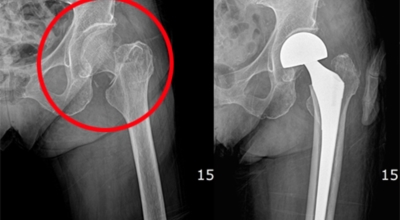

고관절염은 고관절에 나타나는 관절염을 말하며 고관절의 연골이 닳게 되면서 뼈와 뼈가 서로 부딪히며 통증을 일으키게 돼요. 고관절염 초기 증상으로는 사타구니 부위가 불편하게 느껴지며, 무리하면 통증이 발생할 수 있으며, 관절염 증상이 심해지면서 사타구니에서 느끼던 통증이 허벅지와 엉덩이 통증으로 이어지기도 하는데, 고관절염 통증 증상으로 초기에는 허리 통증이 나타나 허리 질환과 혼동하기 쉬우며 각별히 척추질환이 있는 사람은 고관절 통증과 마찬가지로 엉덩이, 다리 통증이 동반되기 때문에 훨씬 헷갈리는 경우가 많습니다.

이 증상은 퇴행성 고관절염에 의해 생기는 현상으로 보통은 중장년층에게 자주 일어나는 질병입니다. 이 질병은 관절과 관절 사이에 존재하는 연골이 닳아 없어지면 관절 내부와 주위에 염증과 통증을 동반합니다. 보통 골반 아래단에 뻐근한 증상을 일으키고 양반다리 자세를 할 때 통증이 심해져요.

더불어 계단을 오를 때 통증이 심해지고 오래 걷는것도 힘들어 져요. 원인은 노화로 인한 연골 마모, 과체중, 고관절 질환을 방치하는 경우 입니다. 치료방법은 적절한 운동과 소염제를 사용하기도 하며 심할경우 수술 치료가 시행 될 수 있어요.

3. 고관절 통증 증상 원인 - 퇴행성 관절염

나이가 들면 예사로 발생되는 질환 중 한 종류입니다. 관절을 지켜주고 있는 연골의 손상이나 퇴행성 변화로 인해 관절을 이루는 뼈와 인대 등에 손상이 생겨 염증과 통증이 나타나는 질환입니다. 고관절 쪽 연골이 닳게 되면서 망가지게 되고 또 쉽게 없어지지 않는 통증에 시달릴 수 있답니다.

고관절 통증 치료에는 크게 약물 치료와 물리 치료가 있어요. 고관절염의 진행을 늦추거나 증상을 개선하기 위한 목적으로 항염증제 또는 진통제를 투여합니다. 고관절 질환의 일부 증상은 체외 충격파, 물리치료, 약물치료 과 같은 비수술 요법으로 증상이 호전될 수 있답니다.

그러나 비수술 치료법으로 개선시키는 것이 어려운 경우 수술적 방법이 고려됩니다. 고관절 통증을 조기에 치료하면 약물치료 외에 물리치료로 약 50% 정도 큰 효과를 볼 수 있어요. 게다가, 보통 고관절 증상 관리에 도움되는 요가, 수영, 스트레칭은 고관절 예방과 치료에 도움 됩니다.